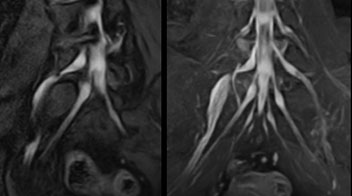

“In such case, we would then browse through axial T2-weighted MR images slice by slice and mentally reconstruct the actual situation based on both radiculography and MRI. Fortunately, NerveVIEW can now very well show nerve courses and presence of nerve compression or edema in one single image series.” “We have often seen NerveVIEW directly depict details of the nerve compression that were not observed by radiculography. Therefore, we think that with NerveVIEW we can reduce the number of invasive examinations, especially for some patients with lumbar plexus symptoms.”

“Before NerveVIEW, diagnosis by MRI alone was sometimes difficult, unless there was a strong suspicion based on clinical symptoms,” says Shoji Yabuki, MD, DMSc, Orthopedic surgeon at Fukushima Medical University School of Medicine. “This is why we routinely perform selective lumbosacral radiculography (nerve root block) and x-ray in such cases. However, radiculography can only depict nerves as far as the contrast agent reaches. When a nerve is distorted by compression, the contrast agent will not pass through this compressed area, preventing us from evaluating the full nerve compression.”

The key concept in MR neurography, Dr. Yabuki stresses, is the ability to directly visualize spinal nerves, versus inferring the presence of pathology indirectly. “Before NerveVIEW, we estimated compression of the nerve by looking for the presence or absence of fat signal on other MR images,” he says.

“For example, in sagittal images, when the presence of fat is observed in the intervertebral foramen, it suggests that there is a margin around the nerve. Similarly, the absence of fat indicates that the nerve is being compressed. So, we used to deduce nerve compression indirectly. With NerveVIEW, however, we can observe the condition of the nerves directly, regardless of the presence or absence of fat. We always prefer such direct observation of anatomy over having to make an inference about it.”

“Although symptoms of typical disc herniation and atypical hernia are very similar, the actual site of herniation is different. It is therefore important to characterize the nerve’s condition both inside and outside of the intervertebral foramina. “Conversely, if we see no abnormality in NerveVIEW, we can assume at least that there is no severe condition that requires surgery. Like this, it can help us avoid unnecessary surgery. NerveVIEW can have a tremendous impact in this way.”

“NerveVIEW is really useful for those cases where a nerve disorder is strongly suspected based on the clinical examination but our regular MRI images do not show any findings. These atypical herniations and spinal canal stenosis, occurring in 5% to 15% of the total lumbar herniation/stenosis cases are our main target when using NerveVIEW,” says Dr. Yabuki.